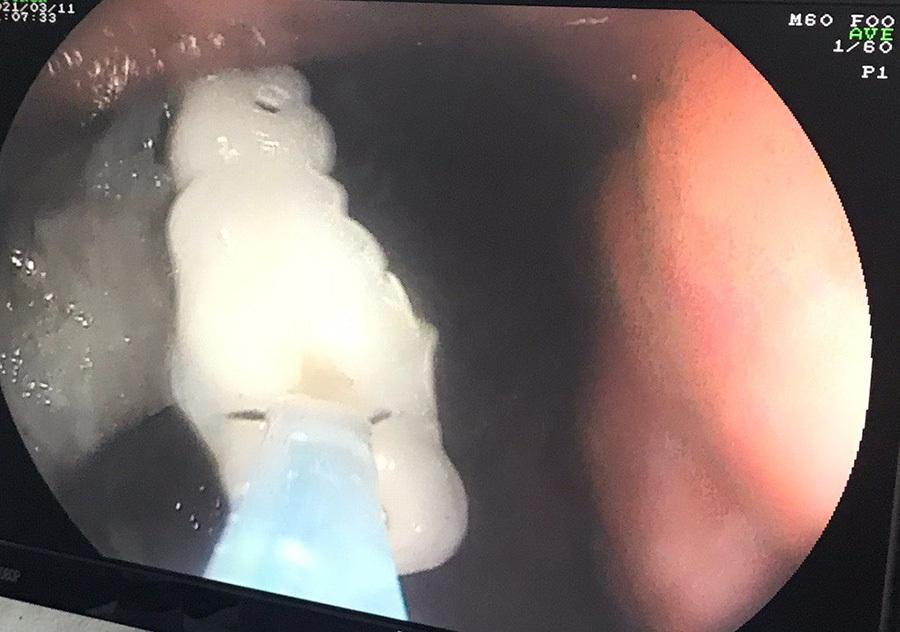

Những chiếc răng giả được bác sĩ nội soi lấy ra từ dạ dày của người phụ nữ 61 tuổi.

Thời điểm cấp cứu, huyết áp của bệnh nhân tăng rất cao. Sau khi bác sĩ xử trí tình trạng tăng huyết áp, bệnh nhân được nội soi tiêu hóa lấy 4 chiếc răng giả. Bà T. được xuất viện ngay sau đó.

"Bệnh viện thường tiếp nhận các ca nuốt răng giả buộc phải nội soi cấp cứu như trên. Móc cài của răng bị mắc kẹt tại vùng hẹp của thực quản nằm gần ngực, nơi có nhiều mạch máu lớn", bác sĩ Mai nói.